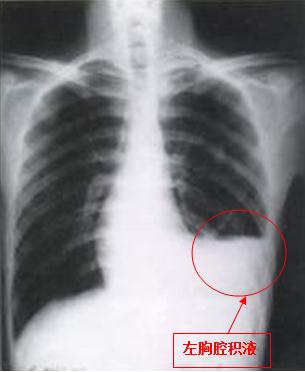

正常人胸膜腔内有3~15ml液体,在呼吸运动时起润滑作用,正常人每天有500~1000ml的液体动态形成与吸收。若由于全身或局部病变破坏了此种动态平衡,致使胸膜腔内液体形成过快或吸收过缓,临床产生胸腔积液,如图: